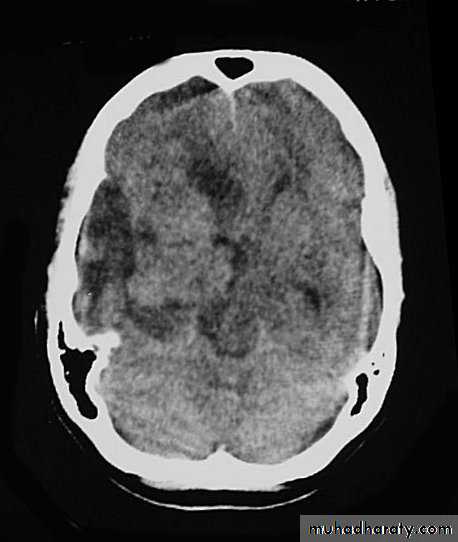

Malignant GliomaPre contrast CT

Malignant Glioma Post contrast CT